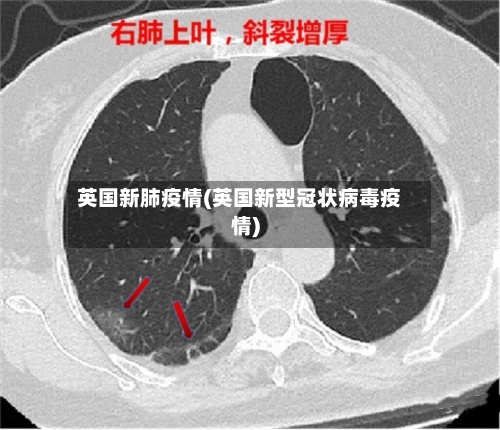

英国新肺疫情(英国新型冠状病毒疫情)